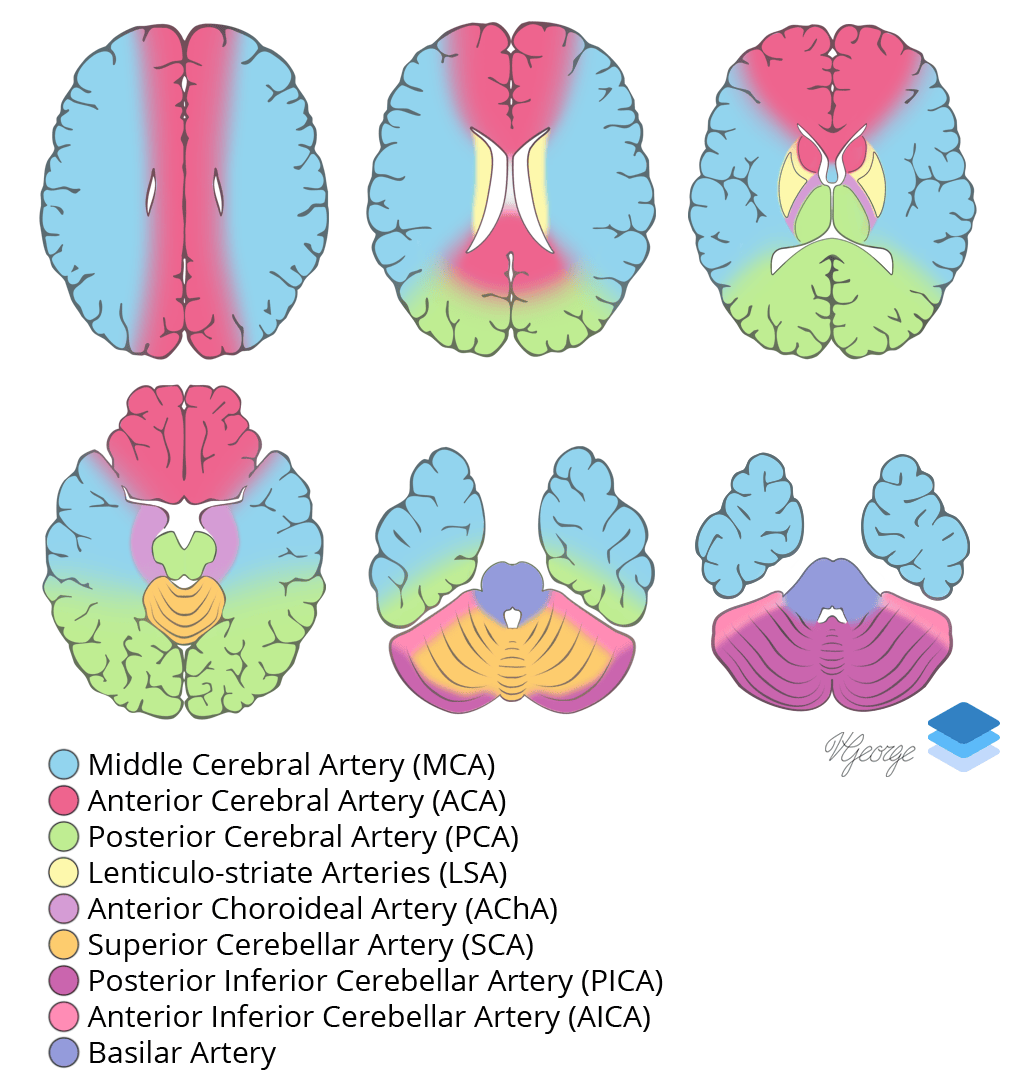

Discussion

- Remember that the thalamus is supplied by the PCA

Cross-sectional arterial territories of the brain.